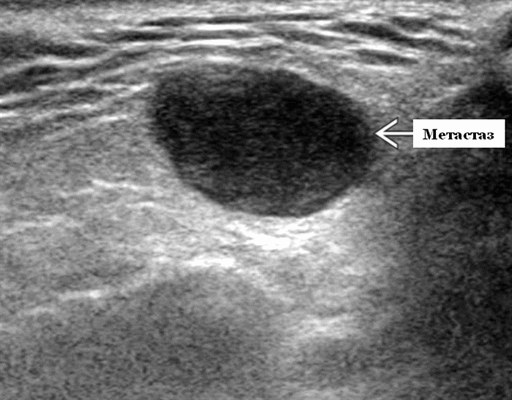

Визуализация. Общие особенности. Само по себе ультразвуковое сканирование метастазов в околоушные лимфоузлы неспецифична. Одиночные или множественные околоушные образования. Хорошо выраженный или плохо выраженный лимфоузел (экстранодальное распространение), однородный или неоднородный с внутренним некрозом. На УЗИ с ЦДК внутриузловая васкуляризация или усиление кровотока. Патология связана с известным первичным раком, часто в прилегающей коже или региональной области головы и шеи. Околоушные и перипаротидные узлы: узловая станция 1-го порядка при плоскоклеточной карциноме кожи (ПКК) и меланоме латеральной части волосистой части головы, ушной раковины / наружного слухового прохода и передней части лица

Размер. Обычно 1-3 см

Морфология. Форма яйцевидная или круглая. Край на УЗИ хорошо выраженный или (при экстранодальном распространении) инфильтративный

Результаты ультразвукового исследования слюнной железы

Серошкальное УЗИ. Одиночные или множественные гипоэхогенные образования в известном распределении внутрипаротидных лимфоузлов. Хорошо выраженный или слабо окаймленный (экстранодальное распространение). Экстранодальное распространение. Обратите внимание на местную инвазию интрапаротидной наружной сонной артерии (ВСА), ретромандибулярной вены или экстрапаротидных мягких тканей. Аномальная внутренняя архитектура ± эхогенные ворота. Однородный или неоднородный вид с внутренними кистозными участками в некротических узлах ± метастазы в шейные лимфатические узлы